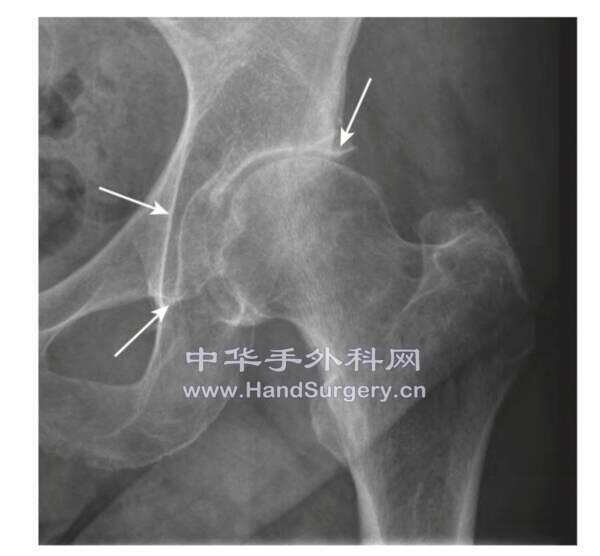

股骨头坏死患者,入院拍片要拍双下肢内旋15°正位片

髋关节置换术测量

1泪滴:泪滴是髋臼四边体和髋臼窝在切线位的成像,其下缘相当于髋臼假体内下缘放置的水平(或稍高);

2髂坐线:加深髋臼时不能突破的底线;

3髋臼外上缘:模型测量时臼杯外上缘的覆盖程度可用于指导和提示术中臼杯放置的位置。如下图可见,若术前测量臼杯外上缘与髋臼外上缘平齐,而术中臼杯外上缘内陷提示可能假体位置异常。